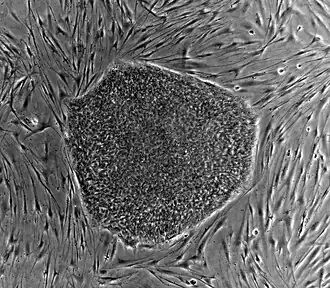

Nearly all research to date has made use of mouse embryonic stem cells (mES) or human embryonic stem cells (hES) derived from the early inner cell mass. Both have the essential stem cell characteristics, yet they require very different environments in order to maintain an undifferentiated state. Mouse ES cells are grown on a layer of gelatin as an extracellular matrix (for support) and require the presence of leukemia inhibitory factor (LIF) in serum media. A drug cocktail containing inhibitors to GSK3B and the MAPK/ERK pathway, called 2i, has also been shown to maintain pluripotency in stem cell culture.[25] Human ESCs are grown on a feeder layer of mouse embryonic fibroblasts and require the presence of basic fibroblast growth factor (bFGF or FGF-2).[26] Without optimal culture conditions or genetic manipulation,[27] embryonic stem cells will rapidly differentiate.

A human embryonic stem cell is also defined by the expression of several transcription factors and cell surface proteins. The transcription factors Oct-4, Nanog, and Sox2 form the core regulatory network that ensures the suppression of genes that lead to differentiation and the maintenance of pluripotency.[28] The cell surface antigens most commonly used to identify hES cells are the glycolipids stage specific embryonic antigen 3 and 4, and the keratan sulfate antigens Tra-1-60 and Tra-1-81. The molecular definition of a stem cell includes many more proteins and continues to be a topic of research.[29]

By using human embryonic stem cells to produce specialized cells like nerve cells or heart cells in the lab, scientists can gain access to adult human cells without taking tissue from patients. They can then study these specialized adult cells in detail to try to discern complications of diseases, or to study cell reactions to proposed new drugs.

Because of their combined abilities of unlimited expansion and pluripotency, embryonic stem cells remain a theoretically potential source for regenerative medicine and tissue replacement after injury or disease.,[30] however, there are currently no approved treatments using ES cells. The first human trial was approved by the US Food and Drug Administration in January 2009.[31] However, the human trial was not initiated until October 13, 2010, in Atlanta for spinal cord injury research. On November 14, 2011, the company conducting the trial (Geron Corporation) announced that it will discontinue further development of its stem cell programs.[32] Differentiating ES cells into usable cells while avoiding transplant rejection are just a few of the hurdles that embryonic stem cell researchers still face.[33] Embryonic stem cells, being pluripotent, require specific signals for correct differentiation – if injected directly into another body, ES cells will differentiate into many different types of cells, causing a teratoma. Ethical considerations regarding the use of unborn human tissue are another reason for the lack of approved treatments using embryonic stem cells. Many nations currently have moratoria or limitations on either human ES cell research or the production of new human ES cell lines.

Human embryonic stem cell colony on mouse embryonic fibroblast feeder layer

Human embryonic stem cell colony on mouse embryonic fibroblast feeder layer